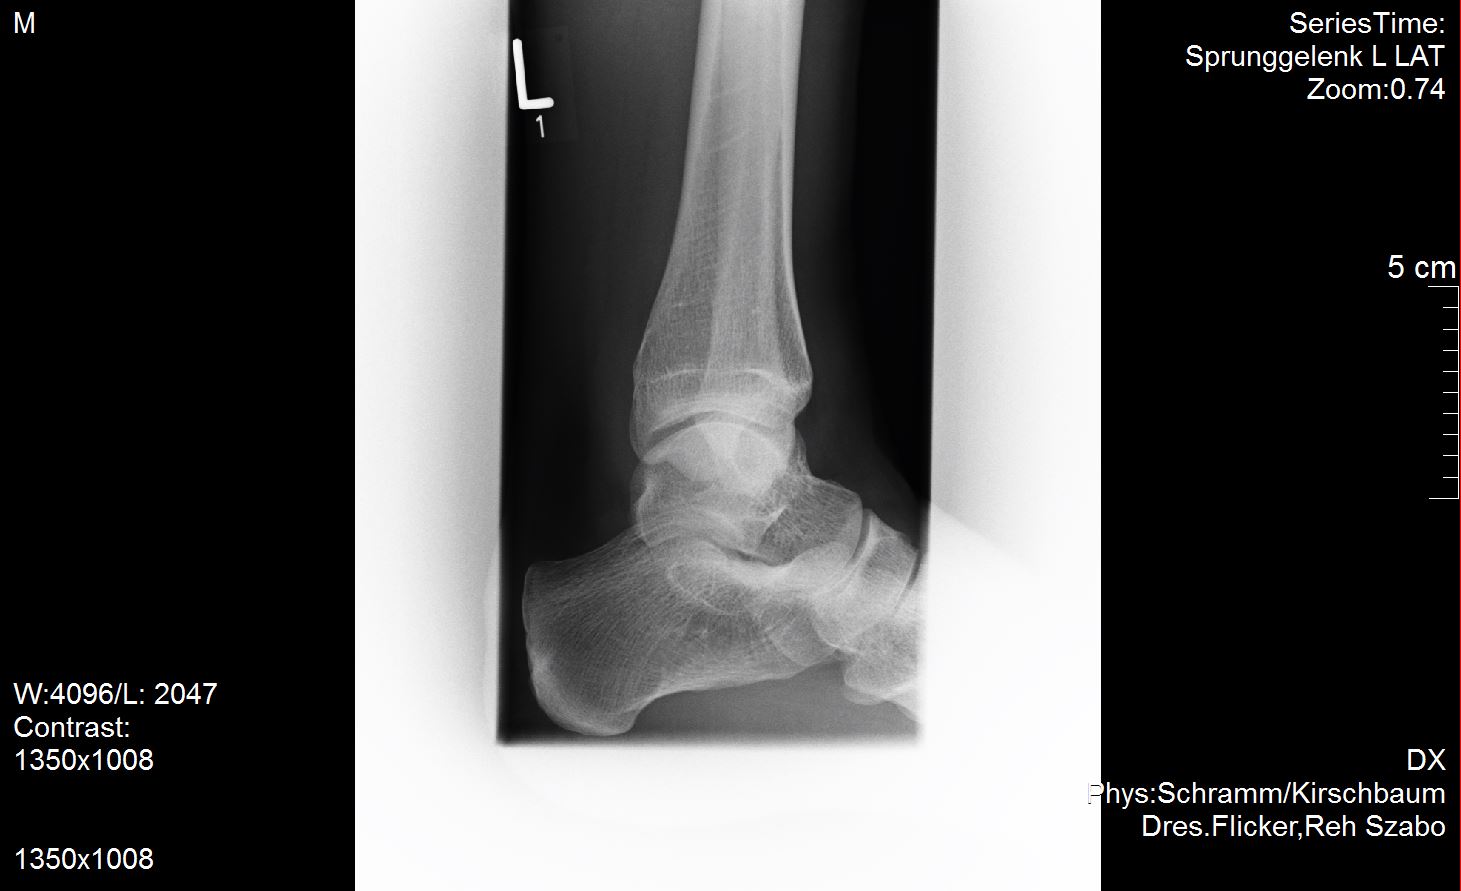

Ich versuche mal meine Röntgenbilder anzuhängen. Vielleicht ist ja ein Experte unter uns der dazu was sagen kann?

Ich habe außer dem mir diagnostizierten Spreizfuß nach oben stehende Zehen. Weiß nicht genau ob man dies Hammerzeh oder Krallenzeh nennt was ich habe aber es geht in die Richtung.